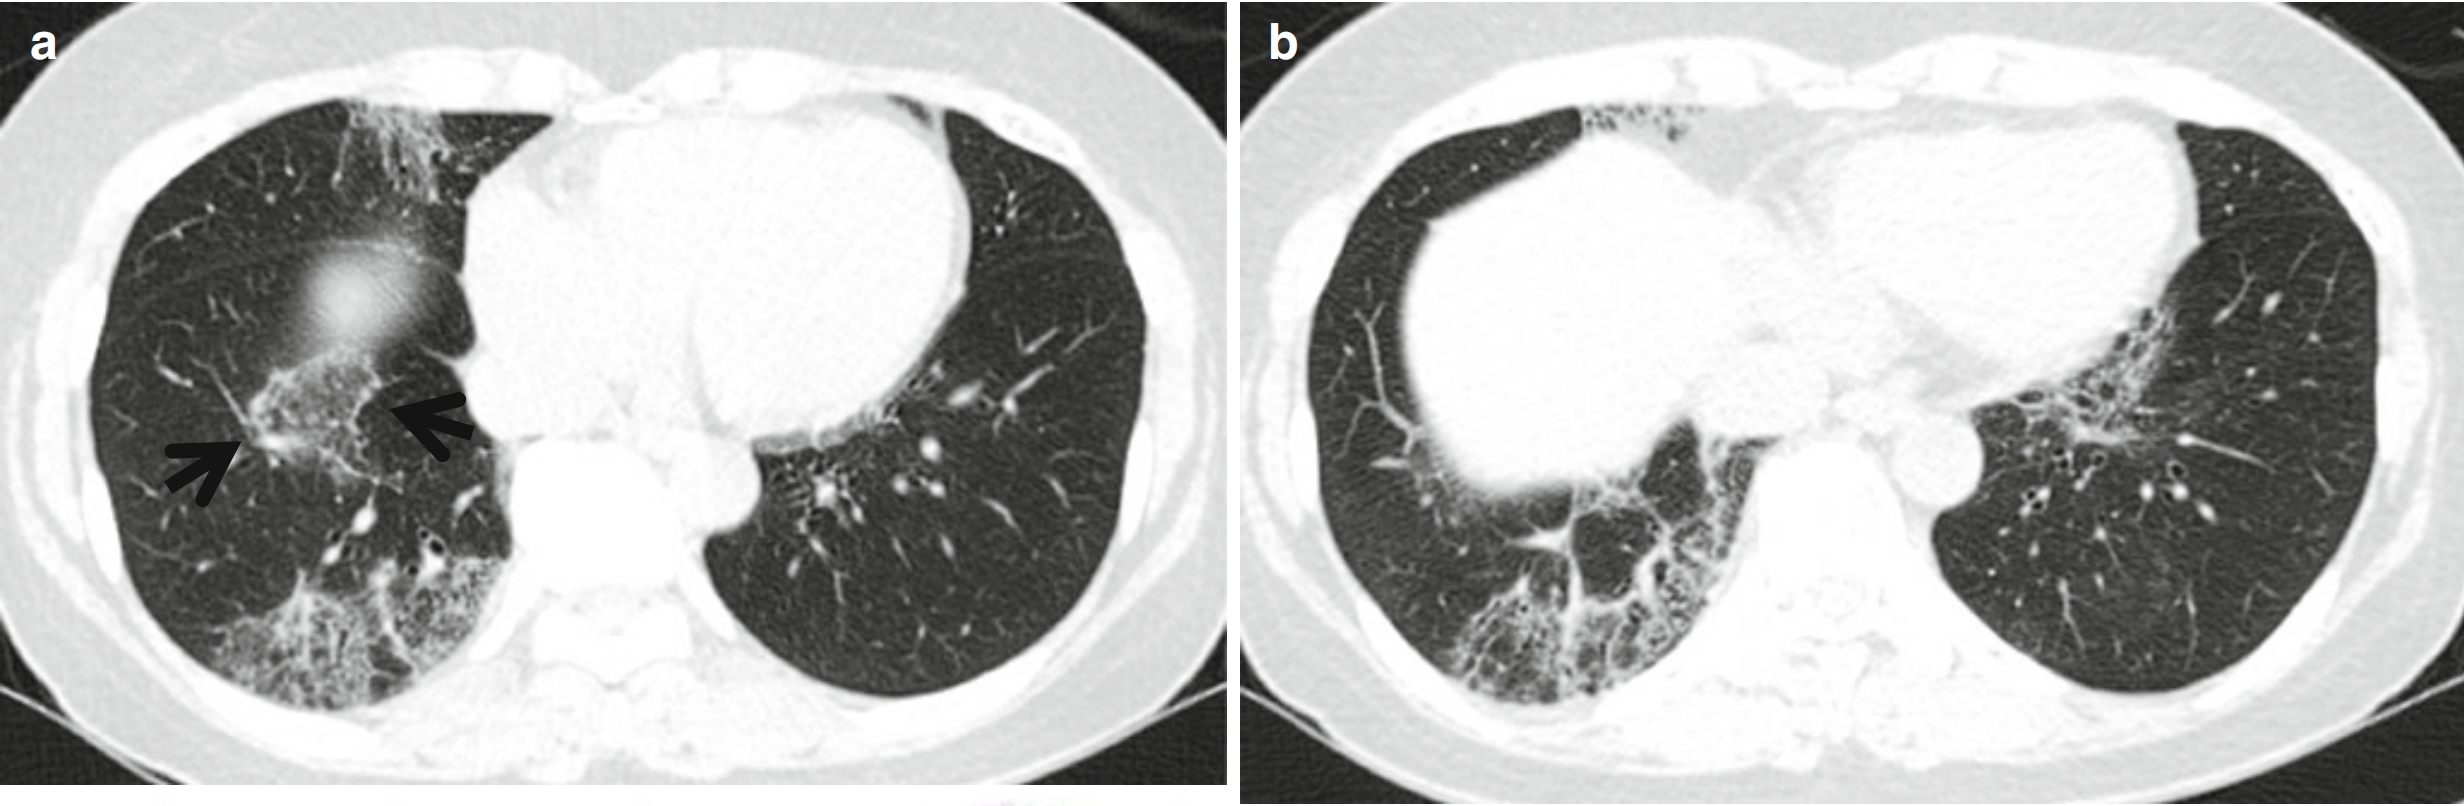

图1 反晕征。女,55岁。哮喘和慢性嗜酸细胞性肺炎患者。(a~c)薄层CT扫描(层厚=1.5 mm)肺窗分别于主动脉弓上层面(a)、主动脉弓层面(b)和奇静脉弓层面(c)示双肺多发局灶性GGO。请注意双肺上叶的反晕征(中央GGO被大致完整的环状实变影包围)(箭头所示)。

反晕征:最初用于描述隐源性机化性肺炎(cryptogenic organizing pneumonia,COP)病灶,表现为局性、圆形GGO周围绕以大致完整的环形实变影(图1)。